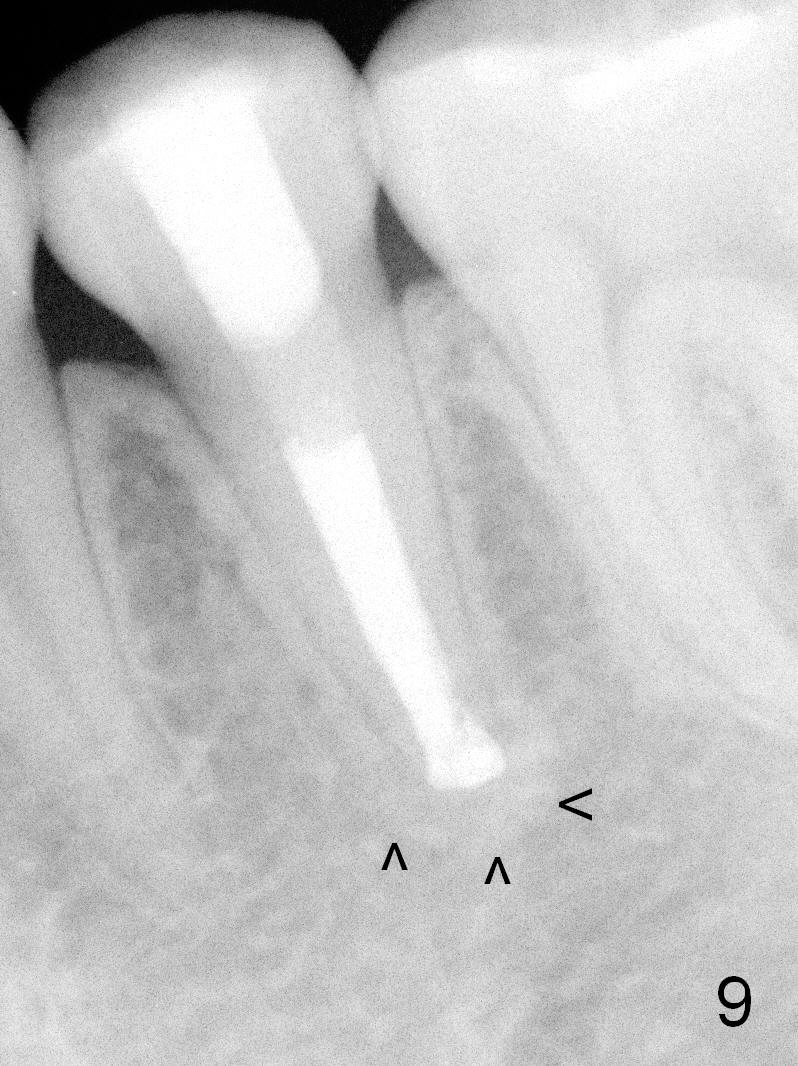

A 13-year-old girl has a buccal apical fistula at the tooth #20 with large periradicular radiolucency (Fig.1 *). After canal debridement, calcium hydroxide paste is placed in the canal (Fig.2 *). One month later, the fistula does not disappear with light percussion. New paste is placed (Fig.3). Two months later, the fistula disappears without percussion. The existing paste (Fig.4) is changed (Fig.5 (yellow: radiolucency; red: Inferior Alveolar Canal)). Another 2 months later, the fistula does not recur; as before, the paste density decreases, so does periradicular radiolucency (Fig.6). Root canal is packed (Fig.7). Six months postop, periradicular radiolucency continues to decrease, while the lamina dura at the apex is discontinuous (Fig.8 between arrowheads). Seven years postop, the lamina dura at the apex is seemingly intact (Fig.9). The patient remains asymptomatic at #20. In fact there is an acute infection at #29.